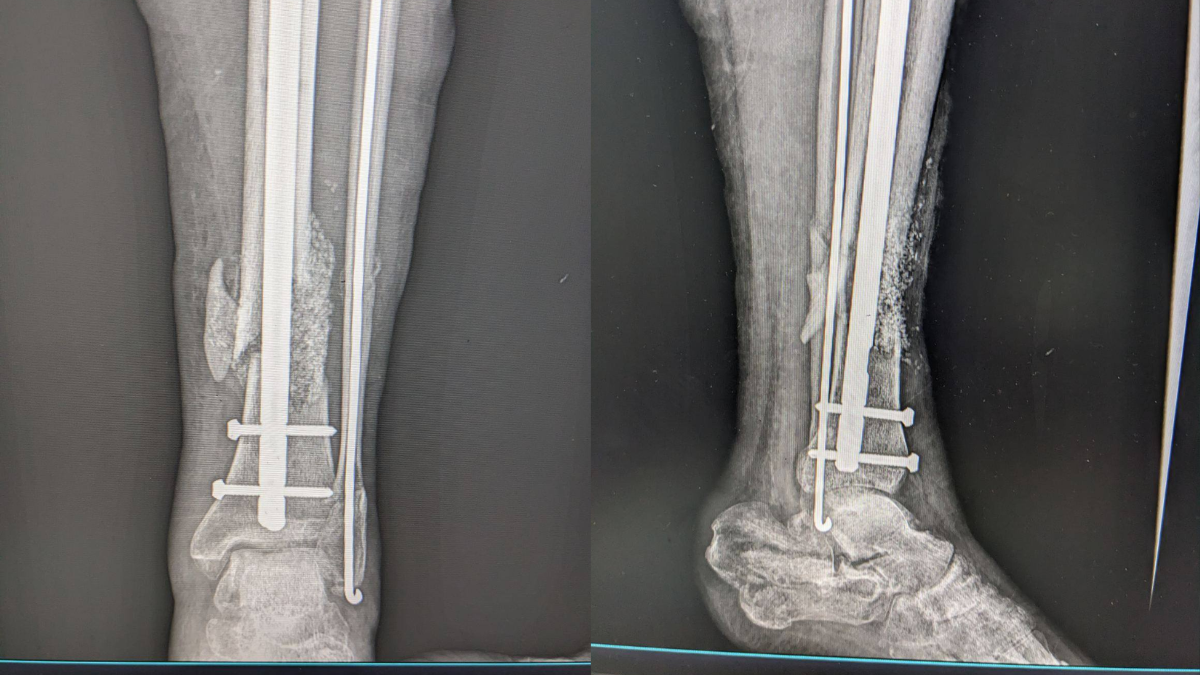

У Богородчанській центральній лікарні військовослужбовцю провели операцію з реконструкції кістки ноги. Для цього використали сучасний матеріал – біоактивне біоскло.

Виконано відновлення цілісності кістки із застосуванням аутокісткової пластики (власна кістка пацієнта) у поєднанні з біоактивним біосклом, повідомили в лікарні.

Використане біоскло було придбане за кошти лікарні, а травматологи-ортопеди проводили операцію з дотриманням сучасних принципів реконструктивної хірургії.